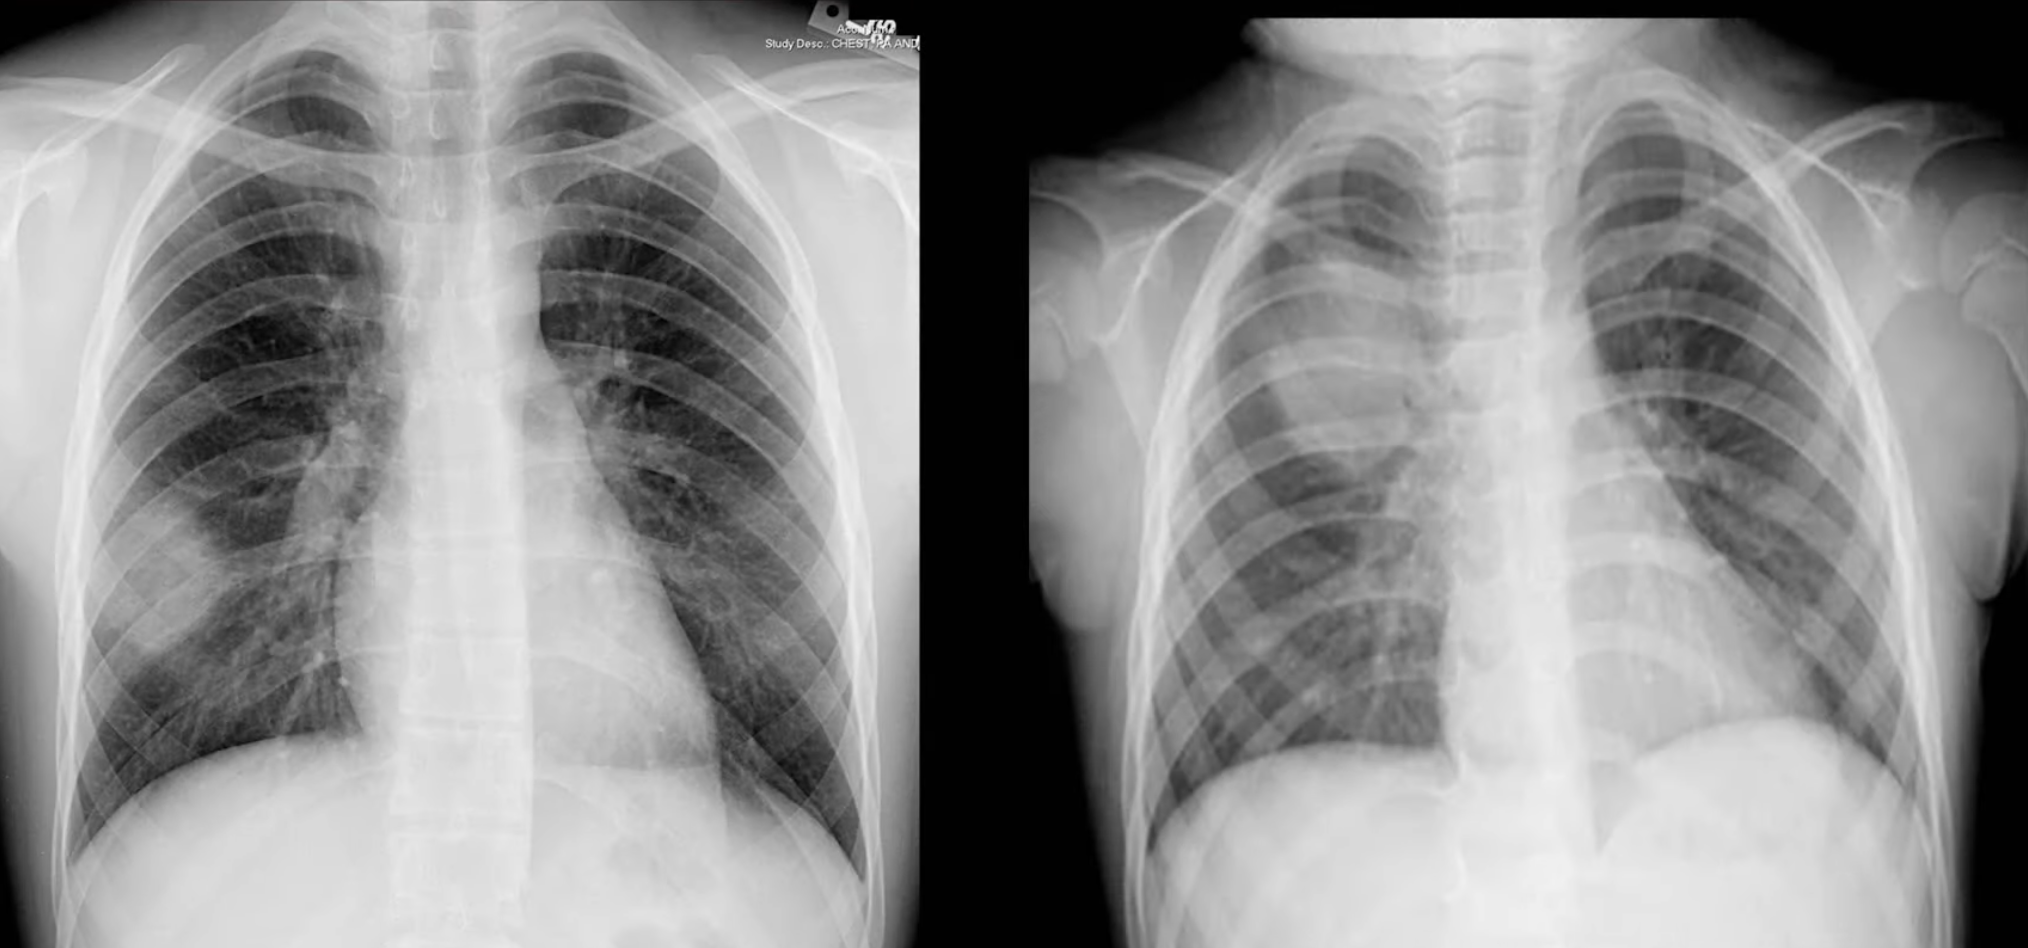

Rotation

Ensure the patient is not crooked (rotated/slumped to one side). Ensure lung apices are visible above the clavicles. Ensure the vertebral spinous processes bisect the distance between the medial ends of the clavicle.

- The spinous processes will be closer to the clavicle on the side that is rotated forward

Penetration

Considered good when the outlines of the vertebral bodies are visible behind the heart (focus on inter-vertebral spaces).